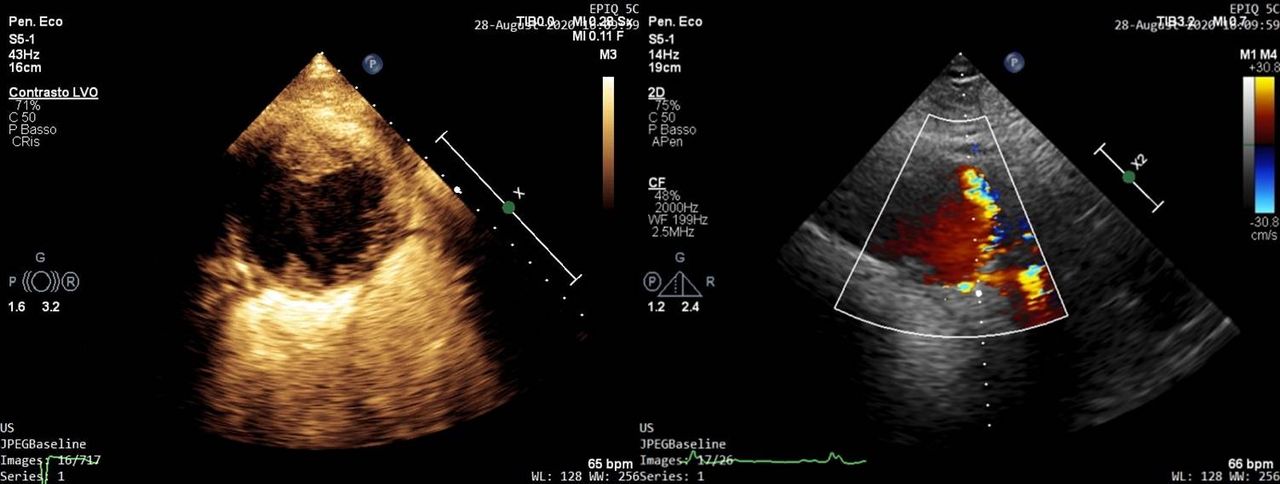

In particolare mi occupo di diagnosi e gestione delle principali valvulopatie mediante esecuzione di ecocardiografia di primo e secondo livello (ecocardiografia transesofagea con particolare focus sull'imaging 3D) e del follow-up dei pazienti presso un ambulatorio dedicato.

Inoltre mi occupo di ecocardiografia con mezzo di contrasto e di ecocardiografia da stress (sia con l'utilizzo di farmaci che con stress fisico-lettoergometro).